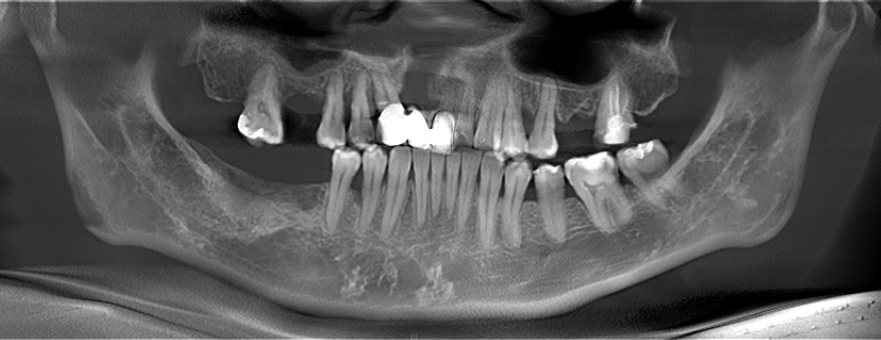

患者在做种植牙术前的ct片

患者做了种植牙后的ct片

如今,倪女士的种植体已经开始和骨头长在一起,16号牙的骨量从1.59mm增长到10.57mm,再过几个月就能装上牙冠。

术前术后ct对比:牙槽骨从1.59mm增厚至10.57mm